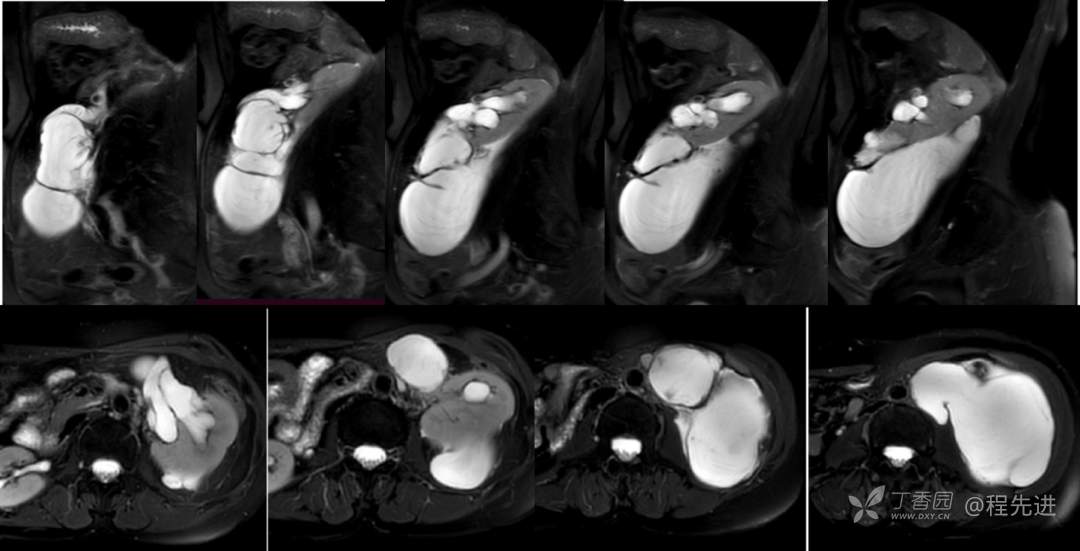

MR增强: